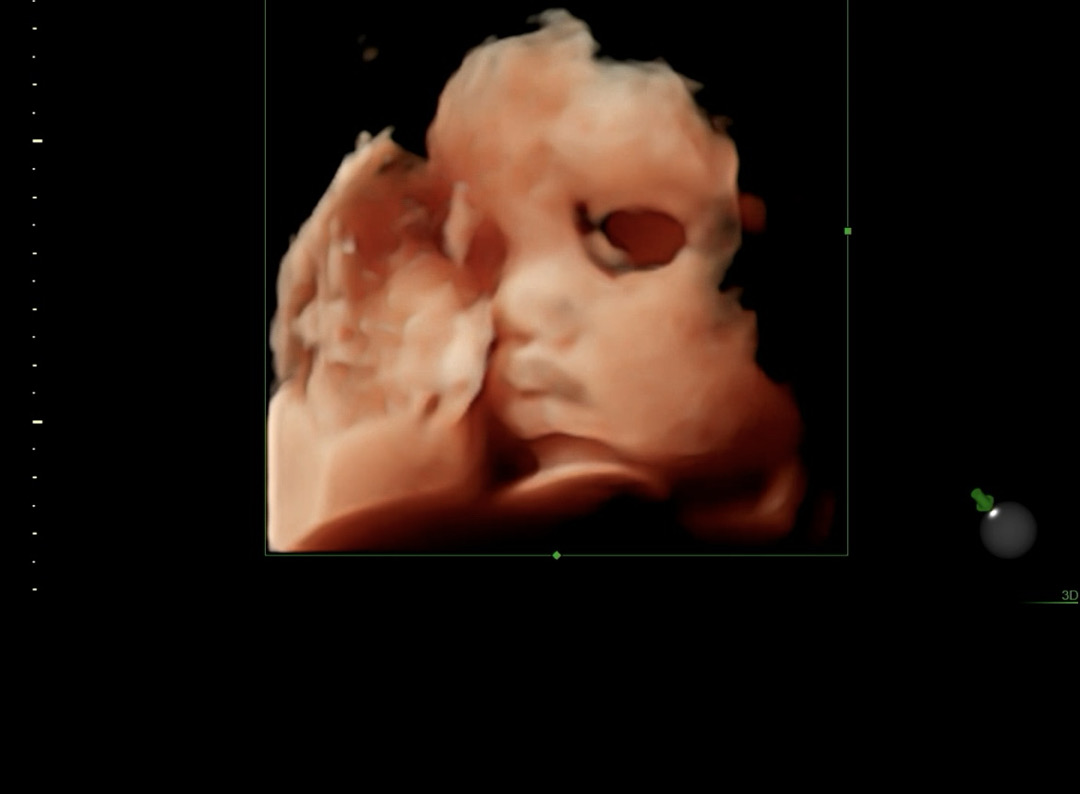

32주4일차 입체초음파!

2.2키로 딸랑구 보고왔어요ㅎㅎ 항상 손빨고 고개돌리고있어서 실패하다가 오늘 운좋게 옆모습 포착했는데 입술 좀 많이 통통해보이지 않나요 ,,,?ㅎㅎ 빨리 만나고싶어요 ㅠㅠㅠ